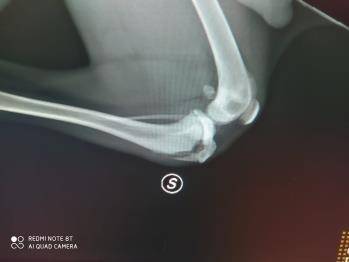

Bill è stato allevato per diventare un campione di caccia. In fase di crescita ha manifestato problemi nell'andatura. Accertamenti veterinari hanno evidenziato "Avulsione bilaterale della Cresta Tibiale" (lesione tipica del cane giovane dovuta al distacco della porzione delle tibia che, essendo in fase di accrescimento non si è ancora definitivamente saldata al resto dell'osso). Il costo dell'intervento e la gestione post-operatoria hanno "scoraggiato" il proprietario che ha pensato di procedere all'eutanasia. Ci è stato chiesto di accogliere Bill e così abbiamo fatto. Bill è stato operato in data 15/02/24, l'operazione è andata bene e ora si trova in stallo casalingo con una persona che si occuperà di lui per il periodo della degenza. Quando Bill sarà guarito per lui si apriranno le porte del canile. Lui è un cucciolone fantastico che saprà dare grandi soddisfazioni a chi lo adotterà. Adottabile in Lombardia o regioni limitrofe.